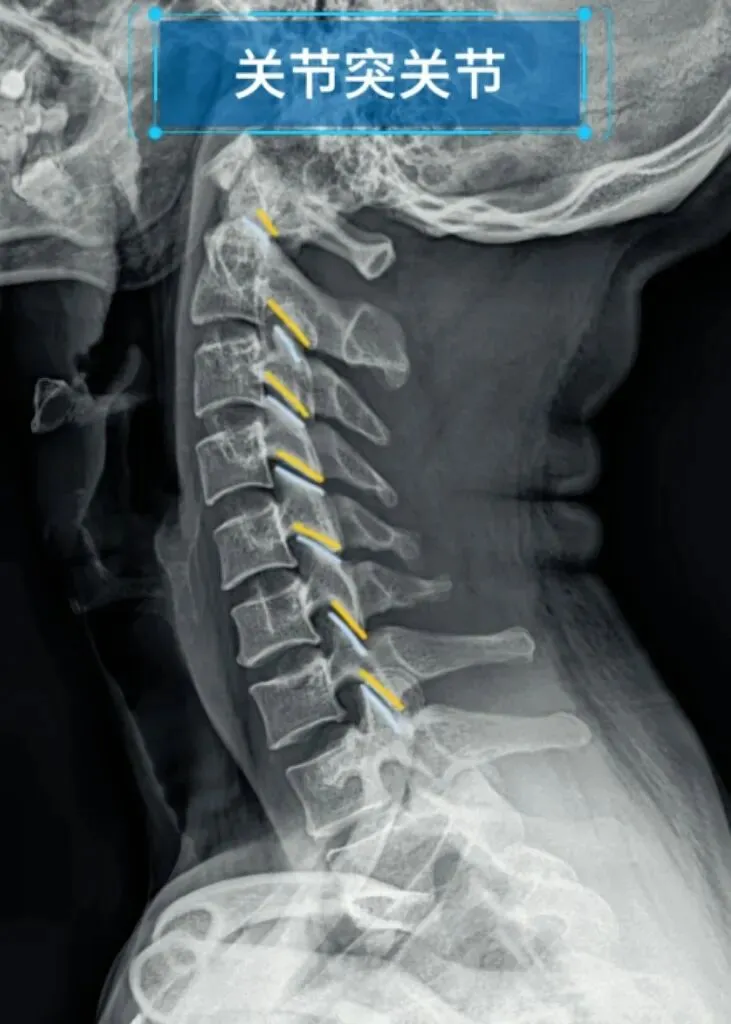

九突指颈椎关节突关节,颈椎上位椎体的下关节突与下位椎体的上关节突构成关节突关节。

若发生病变,可见关节间隙模糊,关节面粗糙硬化,

关节突关节间隙狭窄和边缘骨刺。

关节突关节半脱位多与椎体滑脱并存,关节间隙宽窄不一。